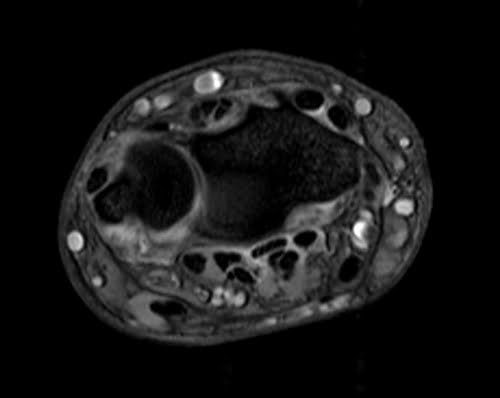

MRI wrist axial medic image 1 - MRI